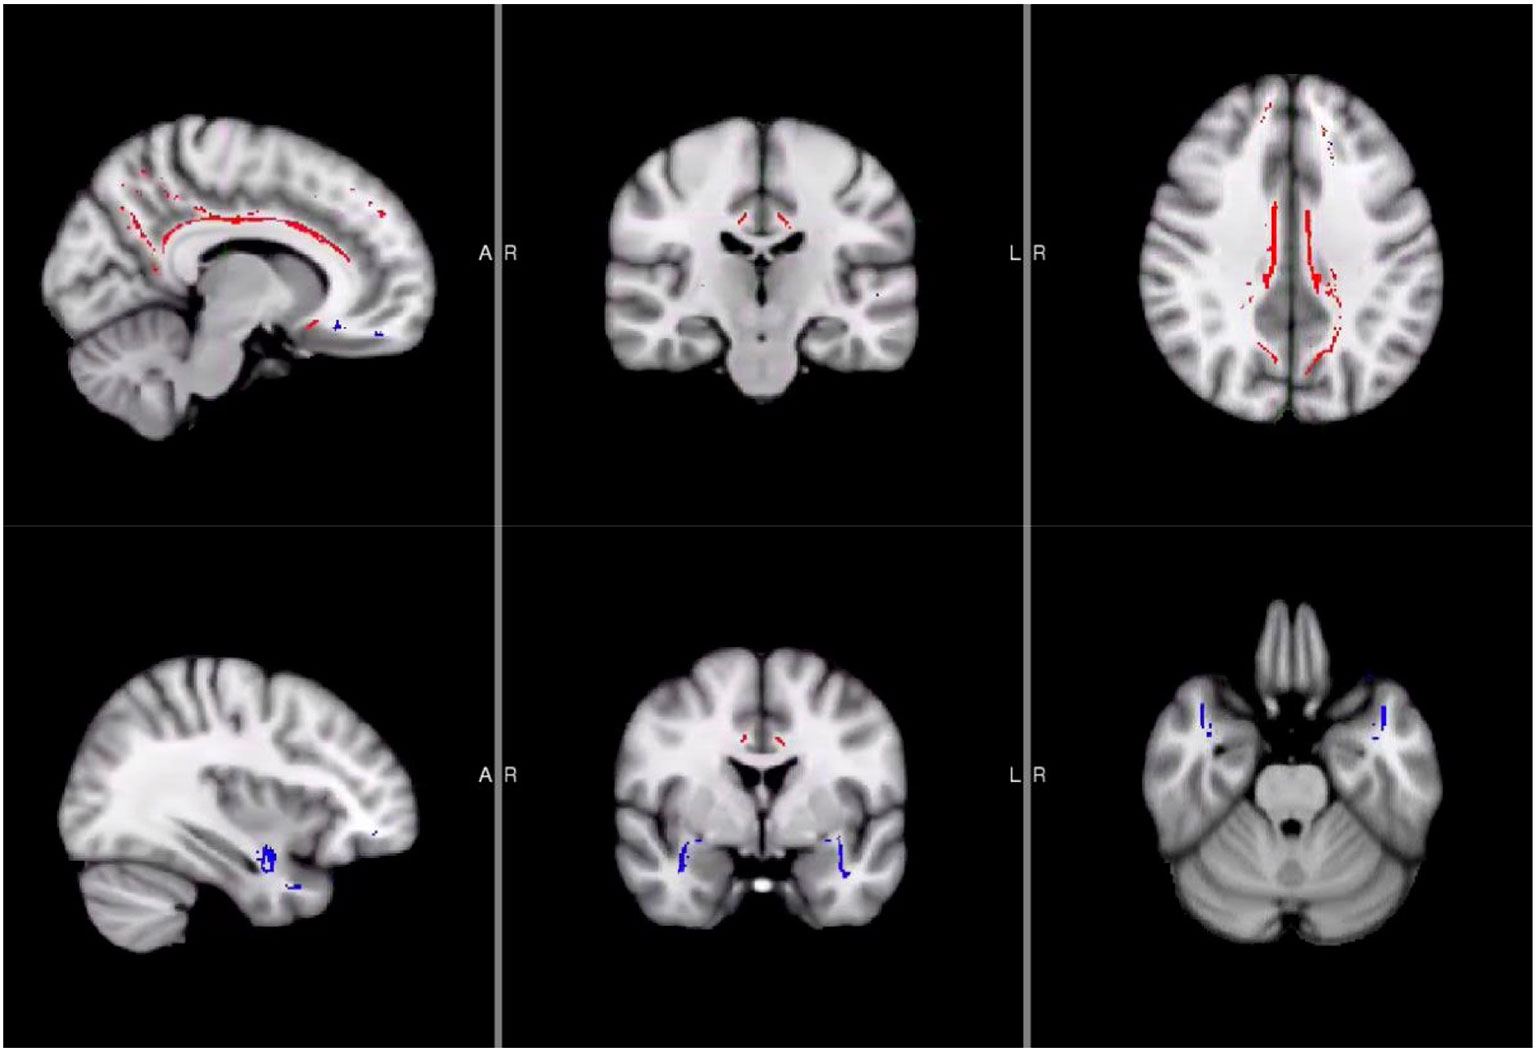

Using the steps for Tract-Based Spatial Statistics (TBSS) in FSL (38), we performed nonlinear registration of the GFA maps into standard space, creation of mean GFA images and a white matter “skeleton” for each individual. This was followed by a projection of the GFA data from all subjects onto the mean GFA skeleton. For the purpose of examining brain-behavior correlates within the NSSI group, the JHU-ICBM-tracts-maxprob-thr0-1 mm atlas was used to create region of interest (ROI) masks for the right and left cingulum and uncinate fasciculus, which are both tracts known to be critical for self-regulation. The ROI masks were multiplied with the GFA mean skeleton to restrict the analyses to voxels within the skeleton and in the tracks of interest (see Figure 1). Finally, fslmeants was used to extract average GFA values within the skeleton portion of each of the four ROIs for all participants for clinical correlations.

Figure 1 Locations of Uncinate Fasciculus and Cingulum Masks. Areas in red were used for the cingulum masks while blue areas were used for the uncinate fasciculus masks.